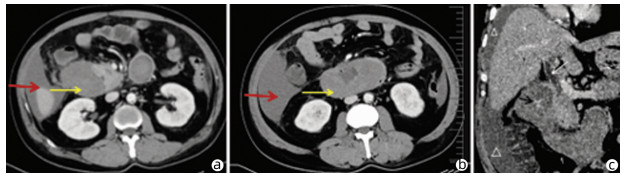

Heterotopic pancreas of the duodenum misdiagnosed as intraperitoneal tumor: A report of three cases

Xing LYU, Jianpeng ZHOU, Kai KOU, Xiaodong SUN, Guoyue LYU

2022, 38(3): 643-645. DOI: 10.3969/j.issn.1001-5256.2022.03.030

Abstract(760) HTML (351) PDF (3871KB)(58)

Abstract: